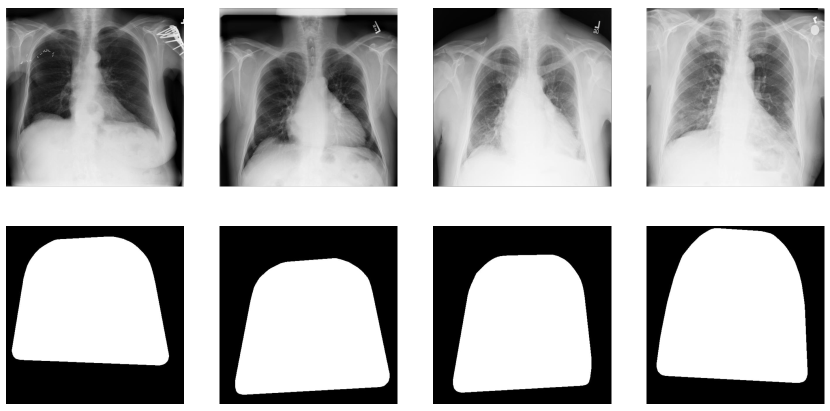

We employ the well-established U-net [34] segmentation model to extract the lung regions from the input CXR images. We train the model using the 247 images from the JSRT dataset [35]. The segmentation model produces undesirable small islands in the case of some images. To address these issues, we binarize and apply post-processing to the segmentation results to remove the unwanted islands based on the anatomical characteristics of the lungs. Since all other islands are small compared to the lung islands, we filter out the largest two islands representing the right and left lung. The sternum region is also important for some thoracic diseases and contains crucial information for classification. To retain this region, we use the convex hull operation [36]. Finally, we use morphological expansion to retain further information from the pleural regions. The overall chest ROI mask generation flow chart is provided in Fig. 2. Some of the CXR images and their corresponding generated masks are shown in Fig. 3. These postprocessing operations are represented by the postprocessing block in the ThoraX-PriorNet full architecture in Fig. I.